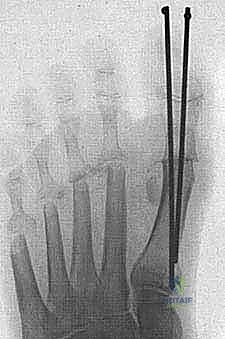

* تُعاد محاذاة أصابع القدم الصغرى وتُثبت مؤقتاً بأسلاك معدنية دقيقة (K-wires) للحفاظ على استقامتها أثناء التئام الأنسجة.

* النتيجة: اختفاء المسامير اللحمية فوراً، تخفيف الضغط عن باطن القدم، واستعادة الشكل المتناسق للأصابع.